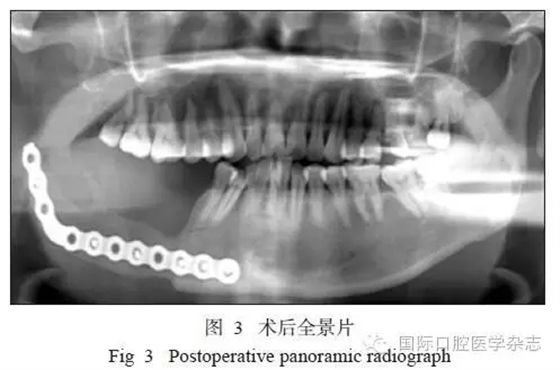

1.5 隨訪

患者術(shù)后切口愈合良好,牙無松動,咬合關(guān)系良好。術(shù)后復(fù)查顯示傷口愈合良好,骨斷端生長良好(圖3)。